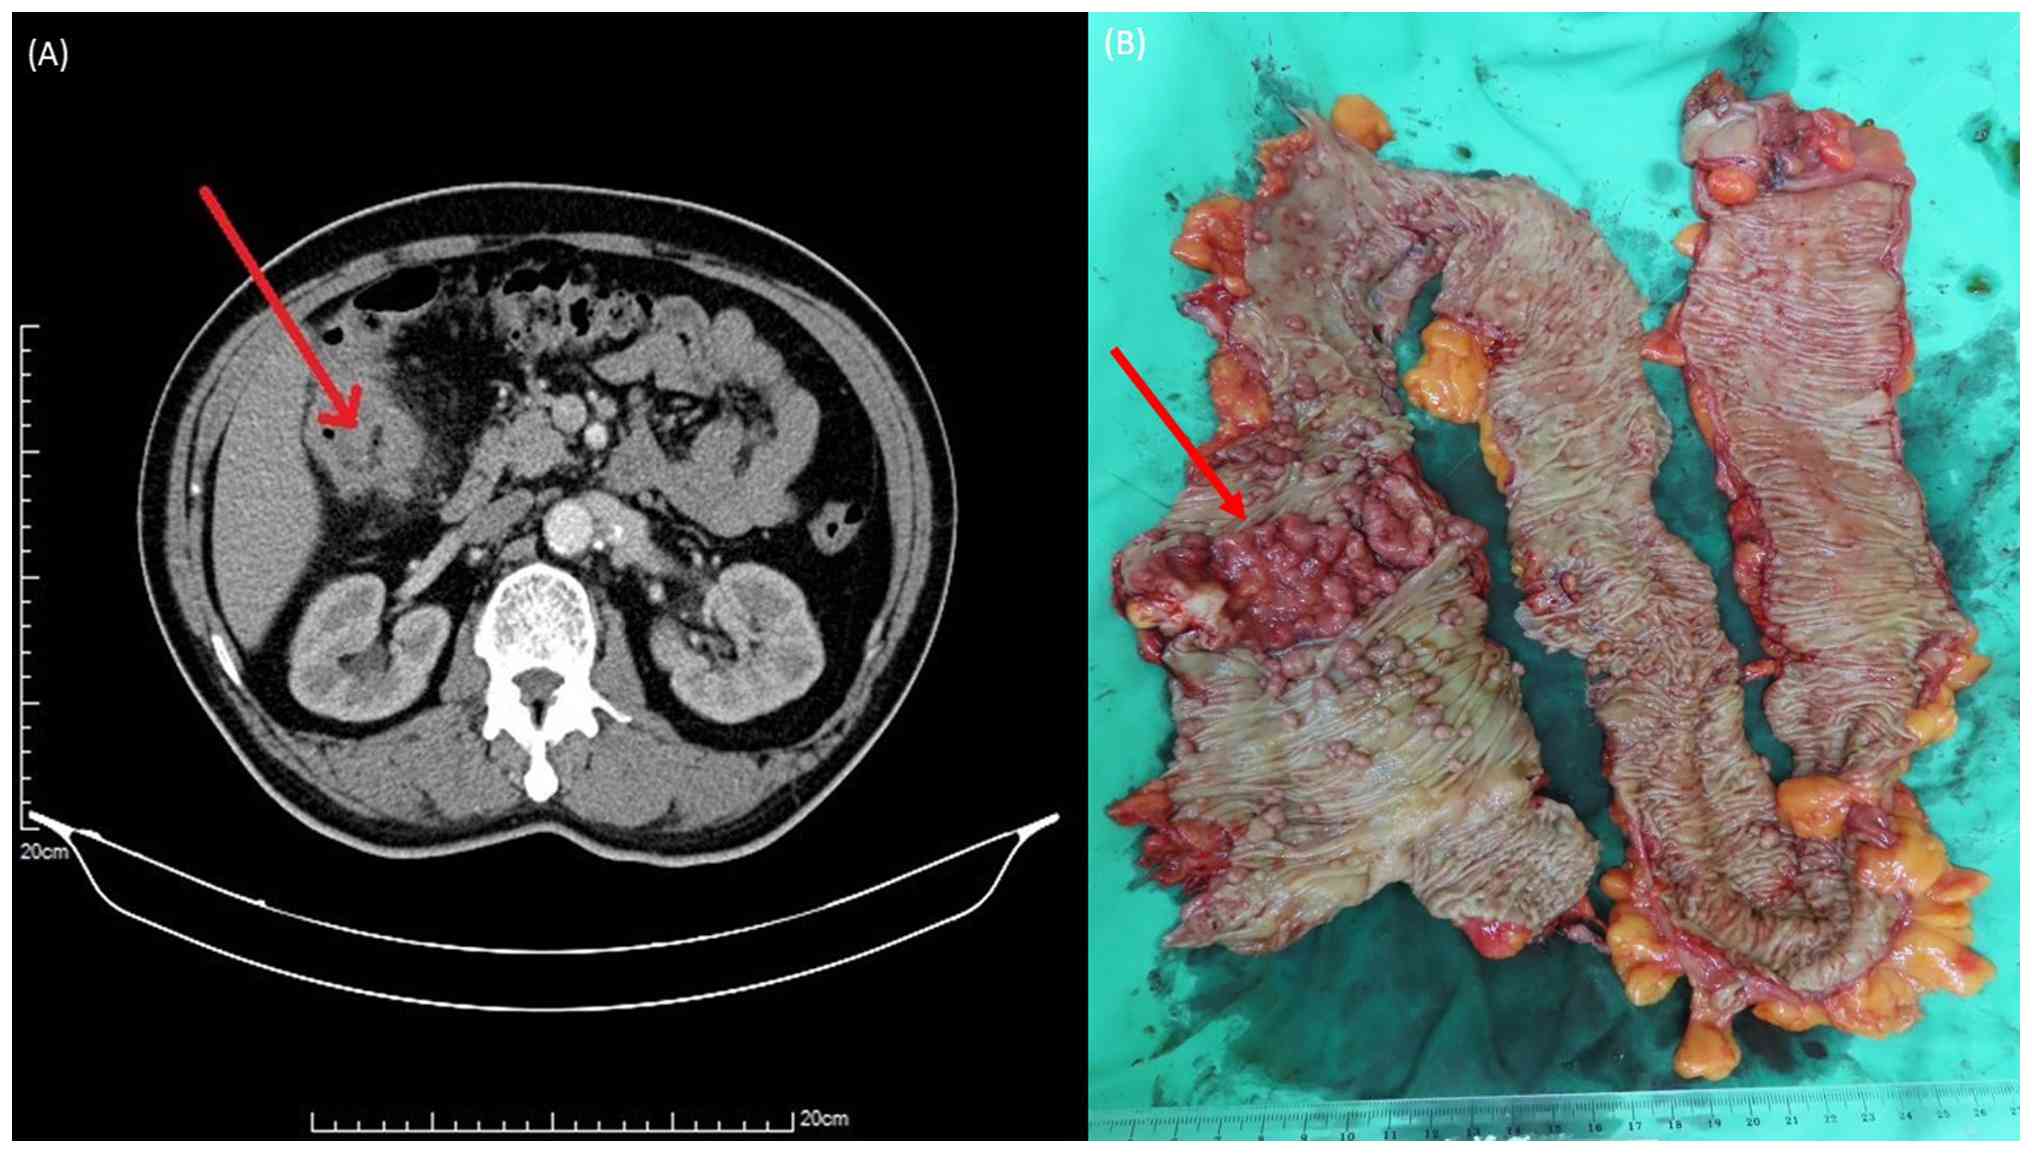

A 63-year-old man with no previous personal or family history of CRC presented to Kaohsiung Medical University Chung-Ho Memorial Hospital (Kaohsiung, Taiwan) in March 2023 with a 1-week history of abdominal pain and hematochezia. A colonoscopy revealed >100 polyps distributed from the upper rectum to the ascending colon (Fig. 1A), along with a suspicious lesion near the hepatic flexure of the ascending colon (Fig. 1B). A biopsy of the lesion confirmed adenocarcinoma. Contrast-enhanced abdominal computed tomography revealed a colonic malignancy at the hepatic flexure with pericolic infiltration, and the clinical stage was cT4bN1M0 (Fig. 2A).

(A) Abdominal computed tomography

revealed a colonic malignancy at the hepatic flexure with pericolic

infiltration, and it was clinically staged as cT4bN1M0 (red arrow;

scale bar, 20 cm). (B) The figure shows the gross appearance of the

excised colon specimen, demonstrating a circumferential ulcerative

lesion at the hepatic flexure (red arrow), consistent with

adenocarcinoma. Multiple tubulovillous adenomas, numbering over

100, were observed throughout the resected colon.

Figure 2

(A) Abdominal computed tomography revealed a colonic malignancy at the hepatic flexure with pericolic infiltration, and it was clinically staged as cT4bN1M0 (red arrow; scale bar, 20 cm). (B) The figure shows the gross appearance of the excised colon specimen, demonstrating a circumferential ulcerative lesion at the hepatic flexure (red arrow), consistent with adenocarcinoma. Multiple tubulovillous adenomas, numbering over 100, were observed throughout the resected colon.

Given the extensive colonic polyposis and confirmed malignancy at the hepatic flexure, the patient underwent a subtotal colectomy with end-to-end ileorectal anastomosis. Postoperative histopathological analysis confirmed a moderately differentiated adenocarcinoma of the hepatic flexure, which was staged as pT3N0M0 (Stage IIA), along with >100 tubulovillous adenomas observed throughout the resected colon (Fig. 2B). Paraffin-embedded tissue sections were stained with hematoxylin and eosin (H&E) according to a standard protocol. Briefly, tissue samples were fixed in 10% neutral buffered formalin at room temperature (~22˚C) for 8 h before being embedded in paraffin. Sections 4-µm thick were cut using a microtome. H&E staining was performed with hematoxylin at room temperature for 10 min followed by eosin for 2 min. Histopathological examination revealed irregular dysplastic glands infiltrating into the submucosa and muscularis propria, accompanied by a prominent desmoplastic stromal reaction (Fig. 3). At higher magnification, the tumor was found to have an atypical glandular structure with nuclear pleomorphism, hyperchromasia and loss of normal glandular polarity within a fibrotic stroma, consistent with moderately differentiated adenocarcinoma (Fig. 4).